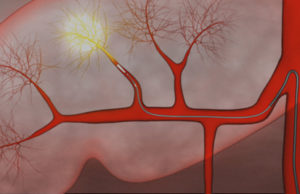

Doctors perform first US bariatric embolization procedure to treat obesity

Bariatric embolization is the first catheter-based procedure that attempts to directly address obesity. The minimally invasive technique is expected to decrease the hormone ghrelin, responsible for appetite, resulting in weight loss.